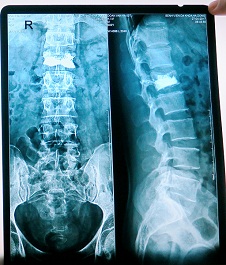

Đốt sống lưng xẹp L1

Đốt sống lưng đã được bơm xi măng

Bệnh nhân là Đoàn Văn Hà 50 tuổi (Trú tại Đại Hùng, Ứng Hòa, Hà Nội ) bệnh nhân nhập viện trong tình trang bị trượt ngã từ dàn giáo trong lúc đang thi công. Lưng và mông đập mạnh xuống đất khiến anh Hà bị đau dữ dội ở phần lưng. Ngay khi tiếp nhận bệnh nhân các bác sĩ tiến hành chụp X- Quang, cắt lớp vi tính cột sống thắt lưng. Kết quả chụp cho thấy bệnh nhân bị xẹp đốt sống thắt lưng L1. Các bác sĩ tiến hành hội chẩn và đưa ra phương pháp bơm xi măng sinh học vào thân đốt sống cho bệnh nhân.

Ngay sau đó anh Hà được chuyển đến phòng mổ và được gây tê tại chỗ, dưới các thao tác của kỹ thuật viên điều khiển máy C-ARM các bác sĩ xuyên một loại kim đặc biệt qua da đi vào thân đốt sống L1 bị xẹp ở lưng, sử dụng bóng bơm làm cho thân đốt sống phồng nên sau đó bơm xi măng vào thân đốt sống của bệnh nhân. Lớp xi măng cứng dần lên chỉ sau 1 giờ bệnh nhân hầu như hết đau, sau 6 giờ có thể tự ngồi dậy, sau 1 ngày tập đi lại bình thường và sau 3 ngày bệnh nhân được xuất viện.